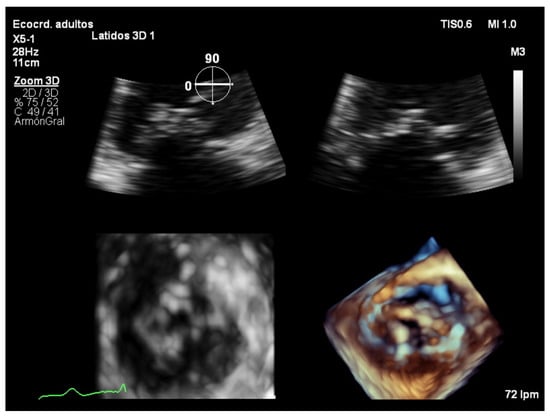

7.2. Full Volume Imaging

7.3. Real-Time 3D Imaging